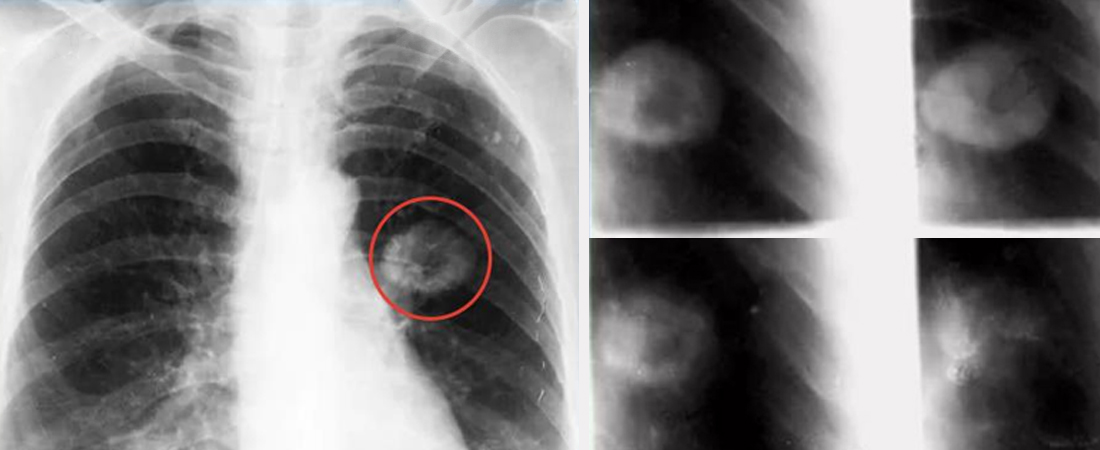

У деяких випадках ліпоми можуть утворюватися не під шкірою, а в органах — печінці, нирках, легенях, серці або навіть мозку. Це рідкісне явище, але воно може бути потенційно небезпечним через компресію навколишніх структур.

Такі ліпоми виявляють випадково — під час УЗД, КТ або МРТ — і не завжди вони потребують втручання. Проте в разі зростання чи появи симптомів (наприклад, порушень серцебиття або дихання) призначається оперативне видалення.

• У легенях — задишка, кашель

Діагностика таких ліпом потребує серйозного підходу та обов’язкової консультації вузьких спеціалістів.